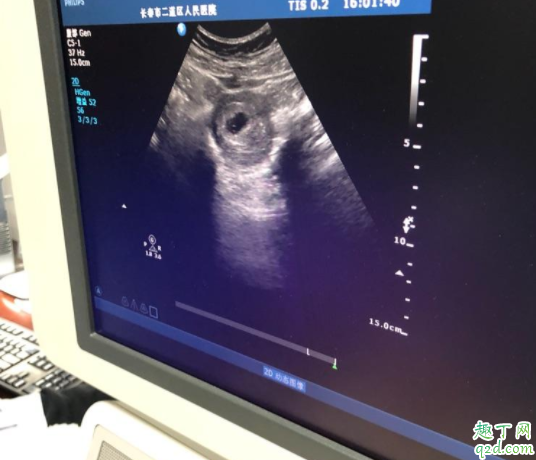

卵黃囊是在懷孕期間妊娠囊中最早出現(xiàn)的結(jié)構(gòu),大概在懷孕5周時(shí)候出現(xiàn)并逐漸增大,給胎芽提供營(yíng)養(yǎng),在12周后逐漸自行消失。

早孕檢查可以做經(jīng)腹部婦科彩超和經(jīng)陰道婦科彩超。兩個(gè)檢查都是同樣的檢查原理,都是利于超聲技術(shù)。只是兩個(gè)檢查的檢查途徑不一樣。經(jīng)腹部婦科超聲需要憋尿,經(jīng)陰道婦科彩超需要排空膀胱。但是經(jīng)陰道婦科彩超干擾更小,能夠早一周看見卵黃囊、胚芽和胎心。